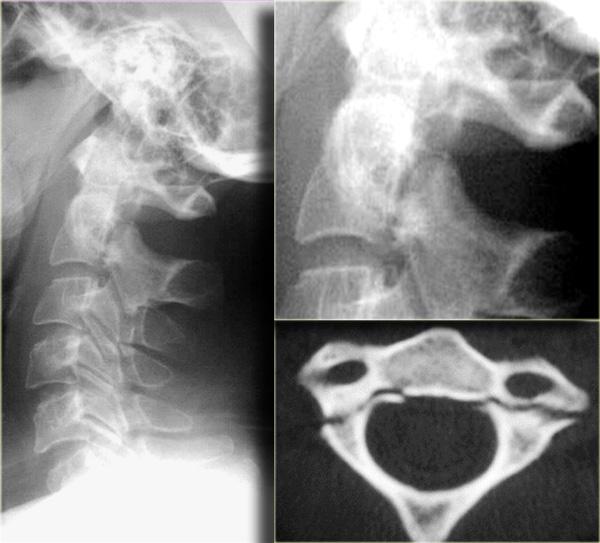

Hình bên trái là hình ảnh gãy mỏm răng loại II không vững.

Hình bên trái là một trường hợp gãy mỏm răng loại III không vững.